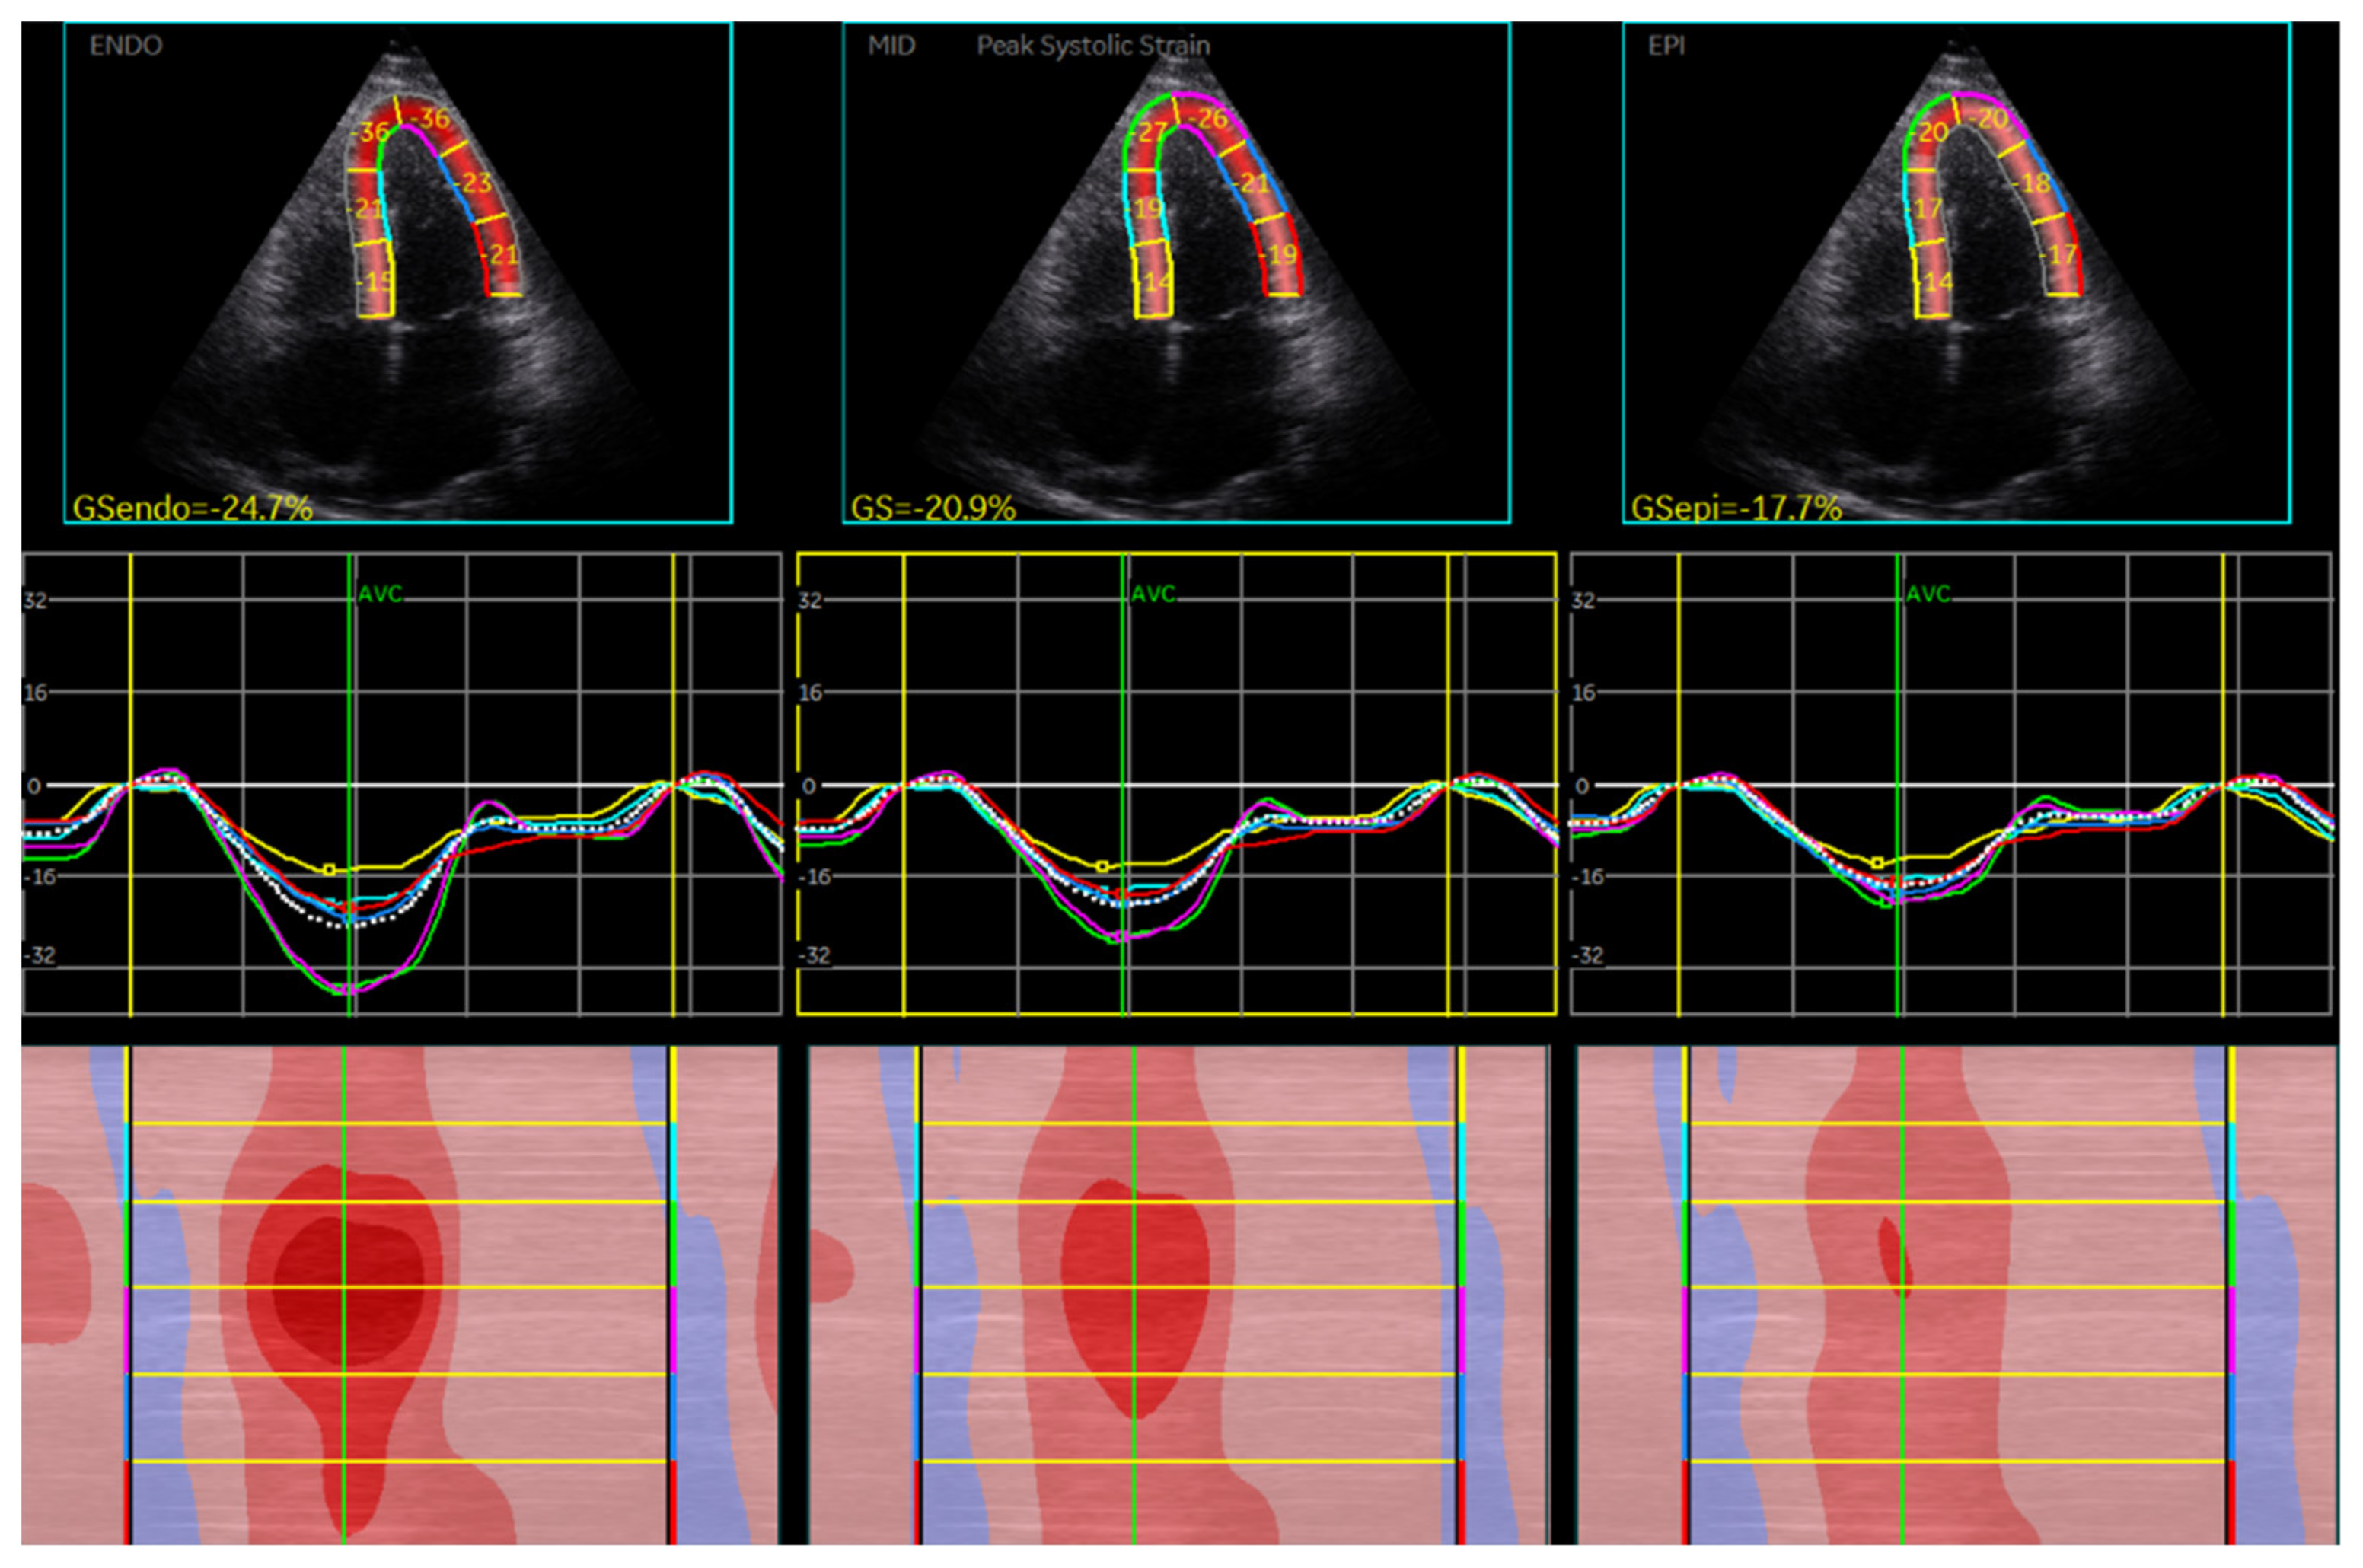

| GLS average | 30 | −18.73 | ± | 2.95 | 80 | −21.39 | ± | 4.06 | <0.001 | |

| GLS mid-myocardial | 30 | −18.56 | ± | 2.63 | 80 | −21.26 | ± | 4.05 | <0.001 | |

| GLS endocardial | 30 | −21.34 | ± | 3.00 | 80 | −24.16 | ± | 4.58 | <0.001 | |

| GLS epicardial | 30 | −16.28 | ± | 2.39 | 80 | −18.75 | ± | 3.62 | <0.001 | |